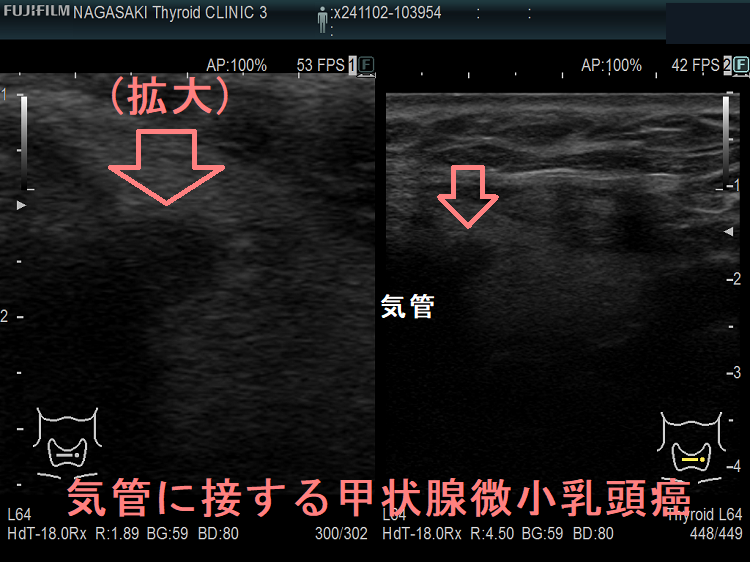

- 気管に浸潤している可能性がある[気管との間に被膜なく、鈍角で(アワビ状に)気管に接している]・甲状腺背面に鈍角で(アワビ状に)反回神経に接する7mm以上の甲状腺微小乳頭癌は、気道内への出血・反回神経麻痺の危険から、甲状腺を半分切除~全部摘出せねばなりません。(Thyroid. 2016 Jan 1; 26(1): 144–149.)(World J Surg 2016;40:523–528.)(下記)

隈病院でも、鈍角で(アワビ状に)気管に接する甲状腺微小乳頭癌(図のA)は、手術適応にしています(Thyroid. 2021 Feb;31(2):183-192.)

上のエコー画像は長崎甲状腺クリニック(大阪)の自験例です。気管に鈍角で(アワビ状に)接していませんが、拡大画像を見れば分かるように、明らかに甲状腺を包む被膜が消失し、気管に浸潤している様に見えます。